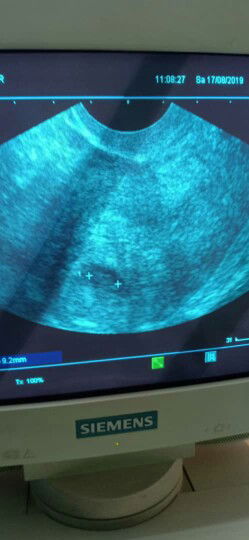

8weeks

Salam..sy nk tanya mumy,sy da preggy 8 mggu...gmba scan yg sy bg tu time 7 mggu..normal ke scan gmba kantung dn baby cmtu?..atau pn tu kira kandungan luar rahim...?kalau kandungan luar rahim utk 7 mggu..scan akan nmpak cm mne eh...sbb hri tu sy ad bleeding skali je..x sakit pn..then pegi hkl doc amek darah banyak kali utk cek..baru2 ni result klua bacaan tggi..kemungkinan besar luar rahim..sy komfius skang ni..mne2 mumy yg penah ad pengalaman bole kongsi x...tq

kandungan 7 minggu

Salam..sy nk tanya...sy ad pergi scan kt hkl mggu lepas..then doc ckp ad kantung n janin...cuma sy nk kepastian dri mumy...utk kandungan 7 mggu janin n kantung mmg nmpak cmni ke..mnx tolong share utk mumy yg ad pengalaman..tq?